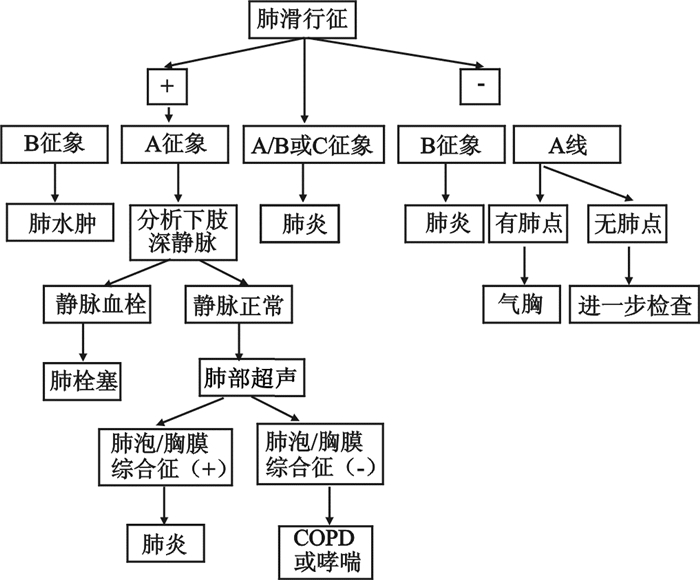

3.2.3 急性呼吸困难超声诊断步骤和流程(1)BLUE草案[21]:2008年Lichtenstein和Meziere率先针对急性呼吸衰竭患者制定了BLUE草案并发表于Chest杂志(图 30)。BLUE草案的主要影像特征为:A表现 仰卧位或半坐位的患者前胸部主要表现为A线,如存在胸膜滑动多见于慢性阻塞性肺疾病、肺栓塞、后背部肺炎;如胸膜滑动消失多见于气胸。B表现 仰卧位或半坐位的患者前胸部主要表现为B线,多见于心源性肺水肿,基本可除外慢性阻塞性肺疾病、肺栓塞及气胸。A/B表现 一侧肺为B线,另一侧为A线,通常见于肺炎。

| 图 30 肺部超声BLUE方案图 |

(2)ETUDES方案[22]:2009年又有学者提出了利用肺部超声B线联合脑钠肽(brain natriuretic peptide,BNP)诊断急性心源性肺水肿的ETUDES(emergency thoracic ultrasound in the differentiation of the etiology of shortness of breath)方案,该方案将双侧胸腔分为8个区域,记录各区域B线数目(图 31),双侧胸壁出现3条以上B线的区域越多,心源性肺水肿可能性越大。如每侧胸壁有3个以上区域均有3条以上B线出现则诊断心源性肺水肿可能性超过90%(图 32)。

(3)CCUS流程[23]:2015年,用于早期诊断急性低氧性呼吸衰竭的CCUS(critical care ultrasonography)超声诊断流程发表于Chest杂志,该草案主要评估B线区域、胸腔无回声区、左心功能及下腔静脉状态(图 33)。根据综合表现判断引起急性低氧性呼吸衰竭的常见病因如肺炎、ARDS、心源性肺水肿等。

近年来国内学者针对国外呼吸困难流程的优劣,结合急诊临床思维,根据超声影像特点分层评估和诊断,制订了优化的急性呼吸困难超声诊断流程(图 34),首先明确有无填塞性的呼吸困难(液、气胸,心包积液);其次区别心源性和肺源性呼吸困难,最后再进一步明确肺源性呼吸困难的原因。与国外的流程相比,更加简洁、快速易于掌握。

| 图 34 改良呼吸困难诊断流程图 |